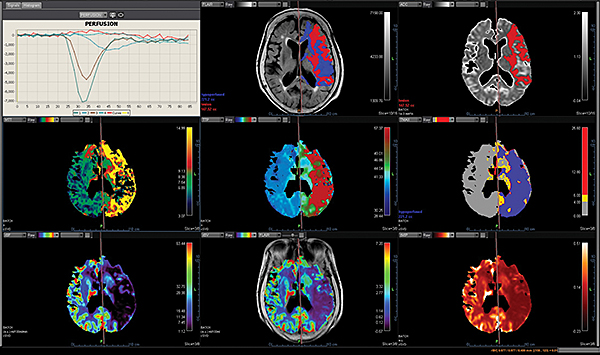

Додаток MR Neuro

Додаток Neuro інтегрований у розширену візуалізацію Vitrea і забезпечує спеціальні протоколи для пухлини мозку та розширені протоколи інсульту, які забезпечують швидку оцінку захворювань головного мозку.

Обчислює оптимізовані параметричні карти (rBV, rBF, TTP, MTT, TMAX, tMIP) із первинної перфузійної серії

Використовує автоматизований та настроюваний робочий процес

Включає повністю автоматизовану поетапну обробку для пацієнтів з пухлинами мозку, включаючи кількісний та якісний мультипараметричний аналіз

Забезпечує корекцію витоку контрасту та створення карти K2 rBV

Пропонує один спеицифічний додаток: Розширений додаток Brain Tumor DSC DCE Expanded